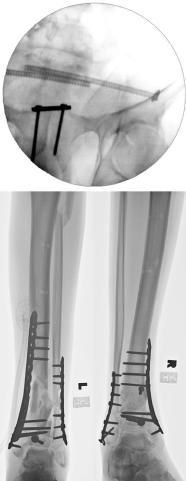

Pre-corrective surgery X-Rays of the damaged right & left legs / ankles

These x-rays were taken at Dr Armendariz’s office, just prior to performing any corrective surgery. As can be seen in these images,

there was no tibia bracing provided by Dr. Keller. Liam was released from Dr Keller’s care with instructions that full weight bearing could

be accomplished within 2 months of Keller’s last surgical procedure. The best example to examine is the second image (from the left) of the

top how. Notice how the bones that should be aligned with the tibia are in fact on the other side of the leg. The third image shows how badly

Liam’s left foot was twisted as a result of the pool placement of the external fixation. What is not obvious is that the screw at the bottom

of the plate on the right fibula missed being screwed into the plate.